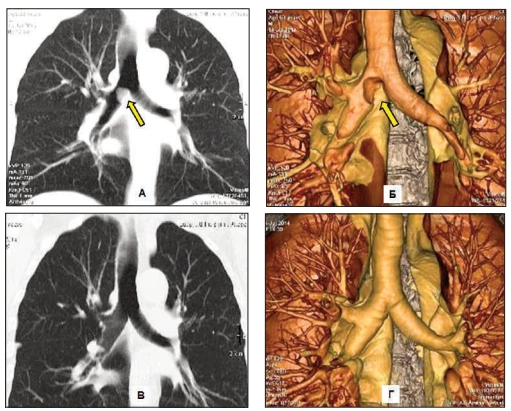

Routine tests miss the "respiratory evil" that Dr. Carson identifies in his functional medicine practice: A dense, hardened layer of old mucus and toxins (PM2.5, tar, heavy metals) that glues the air sacs (alveoli) shut.

"Inhalers only force the airways open for a few hours," Dr. Carson explains. "But in COPD patients, the Suffocation Layer is so thick that oxygen can't penetrate. It's like trying to breathe through a wet sponge coated in asphalt. This is why standard treatments fail."